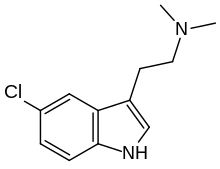

| 5-Chloro-DMT | artificial | 5-Cl | CH3 | CH3 | 5-chloro-N,N-dimethyltryptamine | 22120-32-7 |